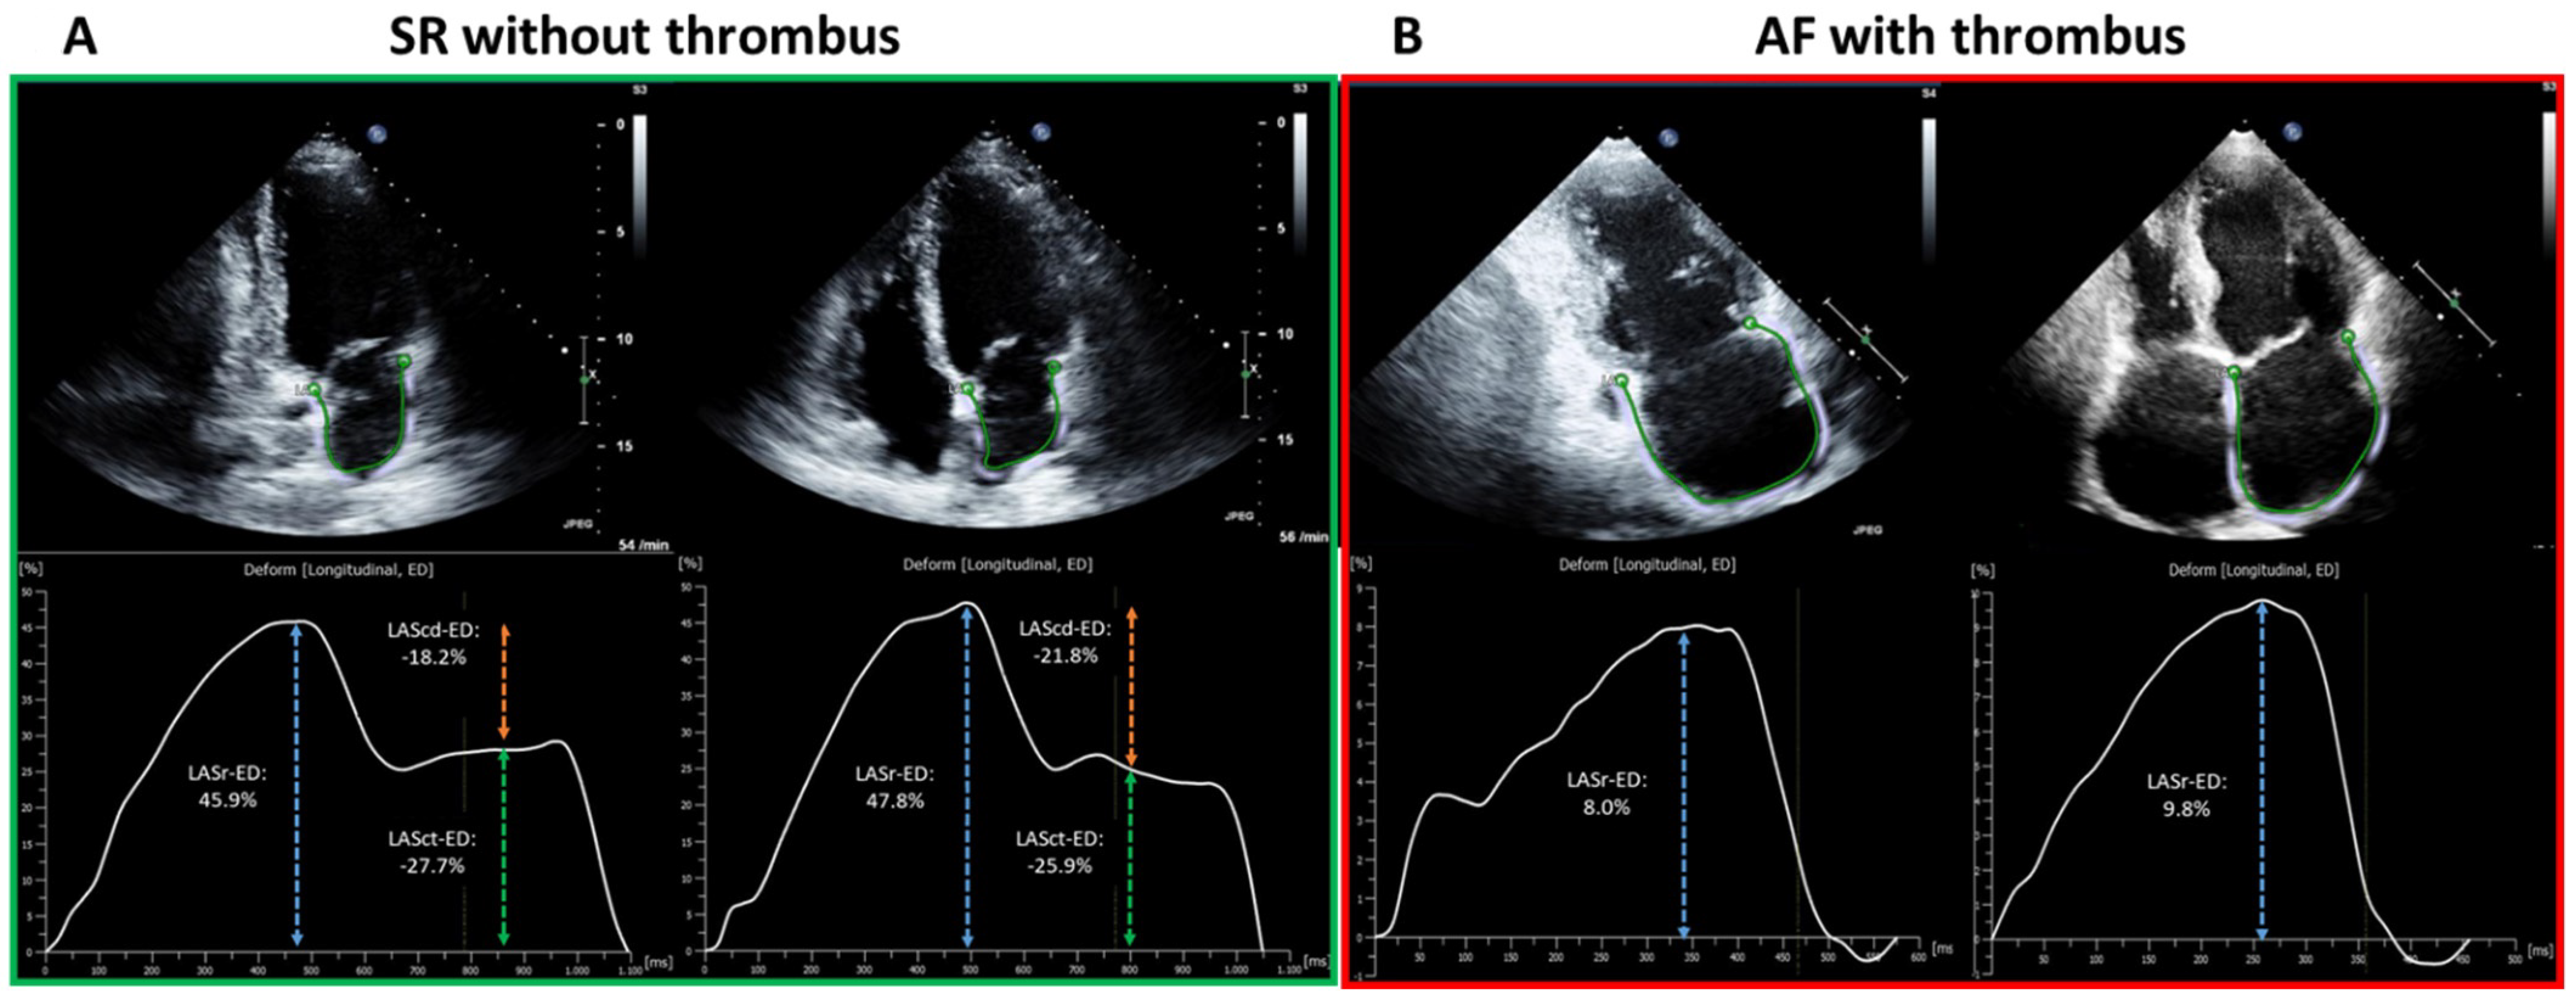

Standardized TTE was performed in all patients in accordance with current guidelines as described previously [11,15]. LA diameter was measured in parasternal long-axis at end-systole. Left ventricular end-diastolic dimension (LVEDD) was measured in M-mode echocardiograms derived from 2D images in the parasternal long axis. Simpson’s method was used to determine left ventricular ejection fraction (LV-EF). Two-dimensional speckle tracking was analyzed in accordance with the current guidelines [16]. For calculation of the LA global longitudinal strain, apical four- and two-chamber views were used (frame rate between 57 and 90 frames per second). LA global longitudinal strain (LA-GLS) was automatically analyzed in four- and two-chamber views using TomTec software (AutoStrain, TomTec Imaging Systems, Unterschleissheim, Germany): A complete R–R cycle (end-diastole to end-diastole) was automatically selected, and endocardial borders were automatically placed by the software. LA-GLS was measured automatically in the reservoir phase (between mitral valve closure and mitral valve opening) and calculated as an average of three consecutive beats from both two- and four-chamber views (Figure 1).

Figure 1.

Illustration of LA-Strain measurement in SR (green outlined left panel, (A)) and AF (red outlined right panel, (B)) from two representative patients. The apical two-chamber and four-chamber view is shown on the left and right, respectively, in each panel. The green curve shows a silhouette of the left atrial endocardium as derived by an automatic border-tracking algorithm. (A) demonstrates the TTE image from one patient in SR without LAA-thrombus on TEE, corresponding results of each plane view are depicted as a LA-strain curve with a composite of LASr (reservoir phase, as in blue dashed arrow), LAScd (conduit phase, as in orange dashed arrow) and LASct (contraction phase, as in green dashed arrow). (B) shows the TTE image of one patient in AF with LAA-thrombus on TEE. In contrast to SR, LASr remains the only strain parameter for measurement in AF (as in blue dashed arrow). The final result of LA-GLS is calculated as the mean results of LASr from two- and four-chamber view of three consecutive heart cycles (end-diastolic to end-diastolic). LA, left-atrial; SR, sinus rhythm; AF, atrial fibrillation; TTE, transthoracic echocardiography; LAA, left atrial appendage; TEE, transesophageal echocardiography; LASr, left atrial strain in reservoir phase; LAScd, left atrial strain in conduit phase; LASct, left atrial strain in contraction phase; LA-GLS, left atrial global longitudinal strain.

LA-strain in SR consists of three components (reservoir strain, conduit strain, and contraction strain), thus achieving a comprehensive assessment of LA contractile function, which has been reported in various studies. LA-strain in AF, on the other hand, was less investigated, as only LA-GLS corresponding to reservoir phase is measurable in this context. In addition, the increased difficulty in identifying the endocardial border in AF has further limited studies on rhythm-specific thresholds. Nevertheless, the difference in LA-strain imaging between SR and AF was observed in the current study (Figure 1A,B). Hereby, awareness should be raised that the inconsistency between SR and AF in contraction patterns and LA-strain imaging reflect the potential underpower of one general threshold for both rhythms in the whole patient cohort, and rhythm-specific thresholds in SR and AF enable further improvement in diagnostic value.